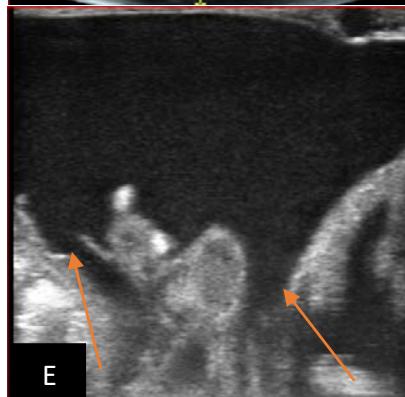

Figure 5: Abdominopelvic ultrasound control after 6 courses of chemotherapy in the same 3 year old patient with a ruptured left renal nephroblastoma; Images A, F, G, and H: show regression of the solid, endo and exo renal, left nephroblastoma mass treated with 6 courses of chemotherapy (current volume 430 ml vs) Images: B, C, and: show persistence of thrombotic permeation pan vena cava and ipsilateral renal. Image E: shows a volumetric regression of the intra-lesional hematic collection, at the tumor rupture estimated at 34.49 ml VS, Image I: represents the right kidney in B mode which is of normal echoculture. Source: Dr. Frederick Tshibasu Tshienda database.

Figure 6: 9-year-old sickle cell patient, referred for abdominal bloating with significant collateral venous circulation, in whom we noted: Image A: mass, Image B: healthy renal stump, inferior polar; Image C: left transmedian extension, Image D: thrombosis of the vena cava segments: supra, retro and sub hepatic, sparing a part of the supra hepatic vena cava segment over $30~\mathrm{mm}$. Image: Ascites of great abundance, Image F: normal left kidney, Image G: splenic microcalcifications, Image H: celiac adenopathy, Image I: sub pleural pulmonary nodules with the biggest measuring $3.88 \times 3.81 \mathrm{~mm}$, Image j: left pleurisy of great abundance. Source: Dr. Frederick Tshibasu Tshienda database.